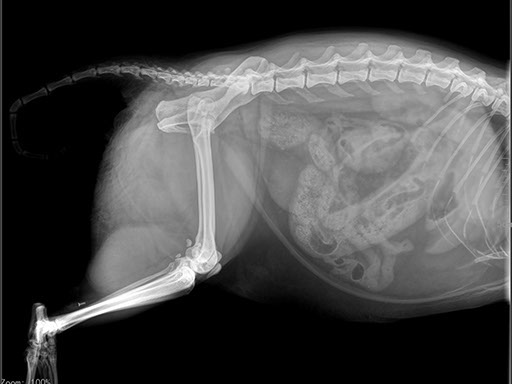

Коллиматорный прицел формирует пучок рентгеновского излучения на участок исследования. Проходя через ткани тела, излучение попадает на плоскопанельный цифровой детектор, который, в свою очередь, передает сигналы на компьютер.

В считанные секунды полученные данные обрабатываются компьютером посредством установленной на него программы визуализации, и сформированное клиническое изображение выводится на монитор лаборанта.

Клинические изображения (снимки) можно напечатать на принтере, сохранить в архиве или отправить по сети коллегам для оперативного консилиума.